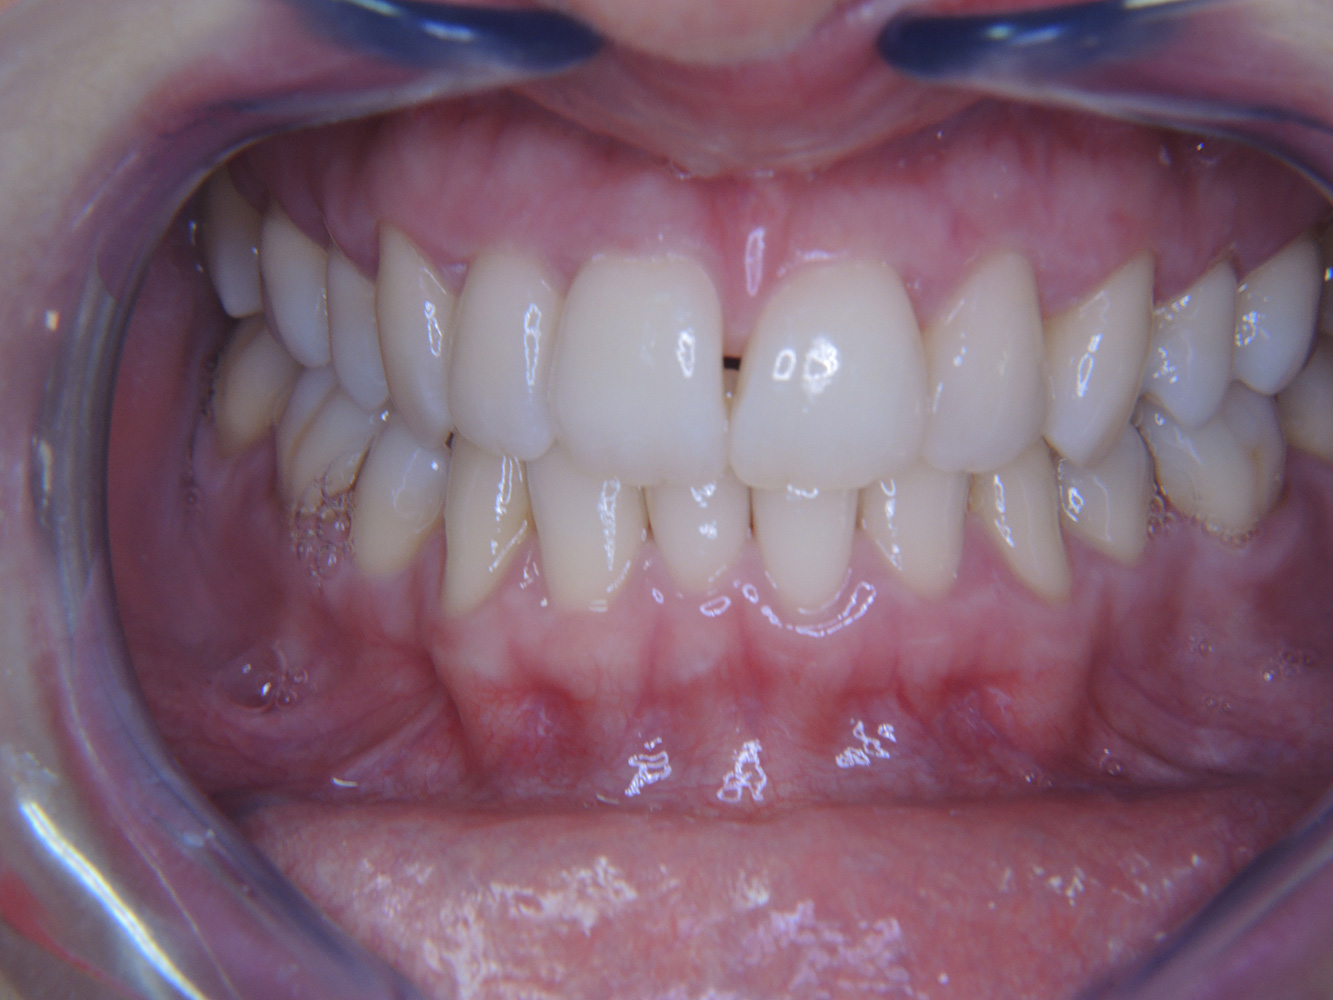

Patientenfälle nach IPCUm das Zusammenspiel der für den IPC definierten Bedarfs- und Risikofaktoren sowie die Auswirkungen einzelner Faktoren zu illustrieren, dienen nachstehende Fallbeispiele*. Die mundgesunde DiabetikerinEine 51-jährige mundgesunde Diabetikerin stellt sich zur Präventionssitzung vor. Die Blutzuckerwerte sind stabil bei einem HbA1c = 6,2%, folglich gilt sie mit dem entsprechenden Medikament Metformin (Antidiabetikum) als suffizient eingestellt. Die Patientin hat keine bestehenden Versorgungen oder orale Vorerkrankungen. Anhand der aktuellen Befunde lässt sich eine Gingivitis bei sonst stabilem parodontalem Zustand (Stage II, Grad B) feststellen. mehr Infos Fallpräsentation: Management komplexer ZahnprothetikEs ist längst bekannt, dass Mundgesundheit und Allgemeingesundheit in direktem Zusammenhang stehen und einen zum Teil bidirektionalen Einfluss aufeinander haben. Die Berücksichtigung beider Faktoren sind bei der Planung der oralen Prävention und Therapie der Patienten in der Zahnarztpraxis unabdingbar. Dabei ist oberstes Ziel, die Gesundheit und die Lebensqualität der Patienten sowohl aus zahnmedizinischer -und medizinischer Sicht zu erhalten. mehr Infos Der (mund)-gesunde Patient mit ImplantatenDer 55-jährige Patient gibt in der Anamnese an, keine Allgemeinerkrankungen zu haben und keine Medikamente einzunehmen. Die Lebensgewohnheiten des Patienten sind ebenfalls unauffällig. Der Patient hat einige zahnärztliche Restaurationen und zwei Implantate (2. und 4. Quadrant). Anhand der aktuellen Befunde lässt sich eine Gingivitis bei stabilem parodontalen Zustand am reduzierten Parodont (Stadium III, Grad A) feststellen. mehr Infos Der gesunde Patient mit parodontaler Vorerkrankung & PeriimplantitisEin 52-jähriger Patient stellt sich zur Präventionssitzung vor. Der Patient hat keine Allgemeinerkrankungen und nimmt keine Medikamente ein. Er hat verschiedene zahnärztliche Versorgungen und zudem zwei aktive kariöse Läsionen. Außerdem verfügt der Patient über vier Implantate (2., 3. und 4. Quadrant). Es zeigt sich eine parodontale Vorerkrankung (Stadium IV, Grad B). Derzeit herrschen stabile parodontale Verhältnisse, lediglich am Implantat regio 36 zeigen sich Sondierungstiefen (ST) von 5 mm. Zudem lässt sich eine Gingivitis feststellen. mehr Infos Der Diabetiker mit ParodontitisDieser Fallbericht eines 52-jährigen Mannes mit Typ-2-Diabetes und Parodontitis hebt hervor, wie durch individuelle Vorsorgemaßnahmen, die Gesundheit des Zahnhalteapparates erhalten bzw. das Fortschreiten der Erkrankung kontrolliert werden kann. mehr Infos Der 28-jährige Raucher mit ZahnerosionenDieser Fallbericht eines 28-jährigen Rauchers mit Zahnerosionen zeigt die Bedeutung personalisierter Patientenprofile. Er unterstreicht die Notwendigkeit, sowohl die Mundgesundheit als auch die allgemeine Gesundheit zu berücksichtigen, um Erkrankungen der Zähne bzw. des Zahnhalteapparates effektiv zu verhindern. mehr Infos Der Endokarditis-Patient mit aktiven KariesläsionenDer Patient ist 39 Jahre mit Z.n. Herzklappenersatz wegen Klappenfehlers und Endokarditis. Als Antikoagulans (Gerinnungshemmer) wird regelmäßig ASS 100 eingenommen. Aus dem Bereich Lebensstil ist die Ernährungsweise als kariesfördernd einzustufen, da mit hoher Regelmäßigkeit zuckerhaltige Lebensmittel sowie sechs bis sieben Mahlzeiten täglich verzehrt werden. Die Mundgesundheit des Patienten zeigt ein mittleres Kariesrisiko mit aktiven Läsionen. Das Parodontitisrisiko ist niedrig, es besteht eine Gingivitis. Es ergeben sich folgende Empfehlungen für die Prophylaxebehandlung. mehr Infos Die gesunde Patientin mit parodontaler VorerkrankungDie 68-jährige Patientin hat keine zahnmedizinisch relevanten allgemeingesundheitlichen Vorerkrankungen oder Medikation, auch aus dem Lebensstil ergibt sich kein besonderes Risiko. Die Patientin hat zwei Implantate (3. Quadrant, seit fünf Jahren) sowie eine parodontale Vorerkrankung (Parodontitis Stadium IV, Grad B) mit Zahnverlust. Derzeit zeigen sich stabile parodontale Verhältnisse. Für die Prophylaxesitzung ergeben sich vier Empfehlungen in den Bereichen Anamnese/Befund, Motivation/Instruktion, der Wahl der geeigneten Instrumente und für Resümee/Folgetermin. mehr Infos

NIWOP – No Implantology without PeriodontologyDer Transplantationspatient mit GingivawucherungenEin 71-jähriger Patient mit Z.n. Nierentransplantation und Hypertonie (Bluthochdruck) stellt sich vor. Bedingt durch die Krankengeschichte ist eine Dauermedikation mit Cyclosporin, zur Unterdrückung der Immunabwehr, und Amlodipin, zur Blutdrucksenkung, erforderlich. Außerdem berichtet der Patient über empfindliches Zahnfleisch und Zahnfleischbluten. Aus mundgesundheitlicher Sicht zeigt sich ein saniertes Gebiss mit acht fehlenden Zähnen, ausgeprägte Gingivawucherungen, eine Parodontitis Stadium II, Grad B mit aktiven Taschen und eine initiale Wurzelkaries an Zahn 22. In der Kariesrisikoabschätzung wird ein mittleres Kariesrisiko (API 60) festgestellt. Für die Prophylaxesitzung lassen sich folgende Behandlungsempfehlungen ableiten. mehr Infos * mit freundlicher Genehmigung von Dr. G. Schmalz und Prof. Dr. D. Ziebolz MSc. Download AreaProxeo Produkte